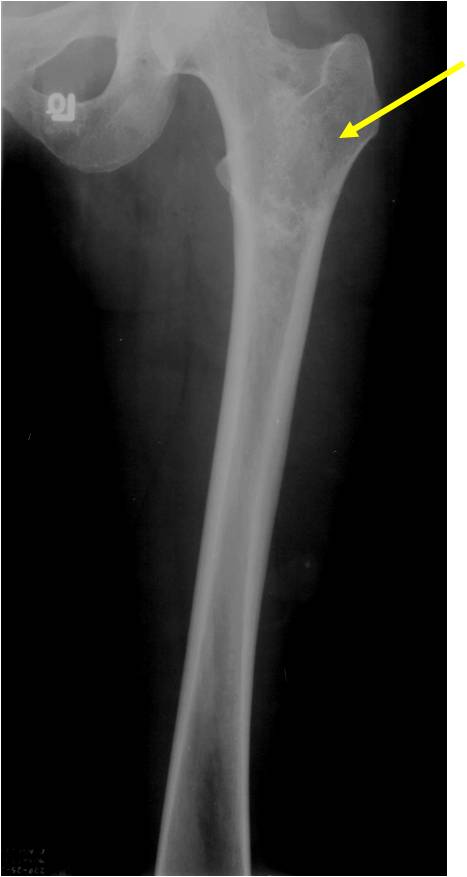

- Localized, radiolucent defect usually with punctate calcifications

- Calcifications are stippled, punctate, popcorn like calcifications and “Ring and Arc” calcifications

- Most commonly found in metaphysis

- Geographic lytic lesion

- Central often metaphyseal in long bones

- Expansile remodeling with thinned cortex

- Chondroid matrix with calcifications in majority of tumors